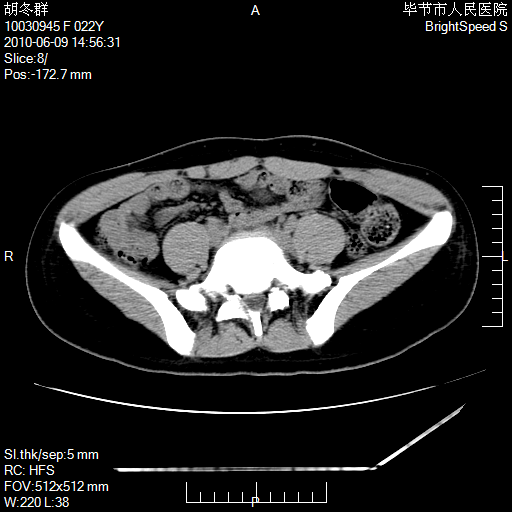

患者23岁,发现腹部包块3月。

盆腔内囊性占位;穿刺或者直接手术拿掉即可,不必紧张。

左侧卵巢囊腺瘤或囊腺癌

盆腔内囊性占位性病变;考虑左侧卵巢囊腺瘤。

有分隔、壁薄,支持考虑左侧卵巢囊腺瘤。

左侧卵巢浆液性囊腺瘤。

支持左侧附件区囊性占位,多考虑为囊腺瘤。

支持考虑左侧卵巢囊腺瘤;宫腔积液。

有分隔、壁薄,支持考虑左侧卵巢囊腺瘤。排尿后,膀胱缩小,由于重力作用,肿块下移就到了膀胱位置,很好理解。